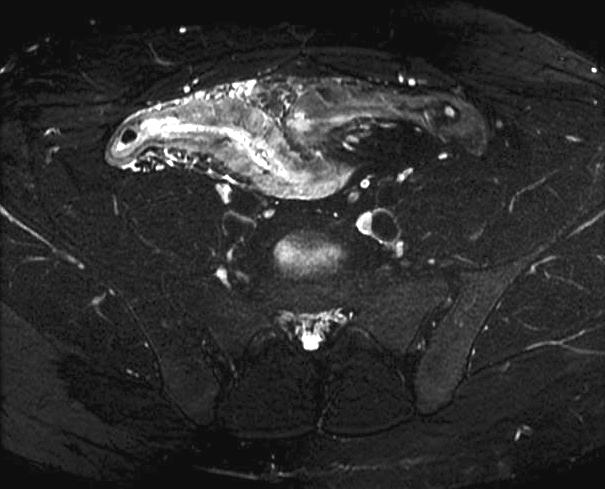

|

Image

radiologique IRM est l'epaissisement parietale

et cette technique c'est le bien pour localisatrice de

lesion . La T2 avec TE court peut

caracterise de l'epaissisement de paroi de l'intestin , de

la differenciation

complex muco-sous muqueux et recherche de oedeme sous muqueuse

. La T1 fatsat peut utilise pour recherche des fistules ,des lesions inflamatoires , lesions fibreuses et des pseudo-polyp

.

Image IRM en coupe axiale T1

fat sat du maladie de Crohn . Epaissisement de la

paroi du colon avec infiltration graisseuse

extramurale du colon . |

Lesion epaissisement de

l'intestin , aspect hypervascularisation en peigne

et fistule entero-vesicale . Infection urinaire

recidivante avec epaissisement de la paroi du vessie

. Image IRM en coupe sagitale . |